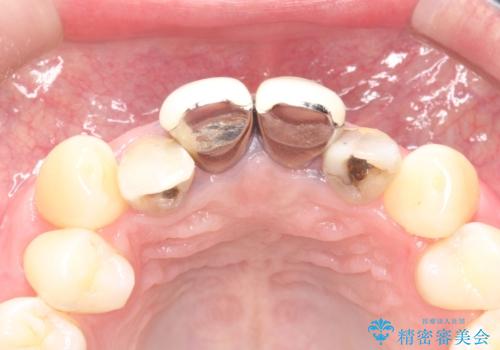

- 上の前歯の見た目が気になるとのことで来院されました。

上の前歯の4本が神経の処置がされており、前から2番目の歯が内側に入り込んでしまっていました。

また、金属で治療された根本の歯茎が黒く変色(メタルタトゥー)しており、余計に見た目がよくない状態となっておりました。